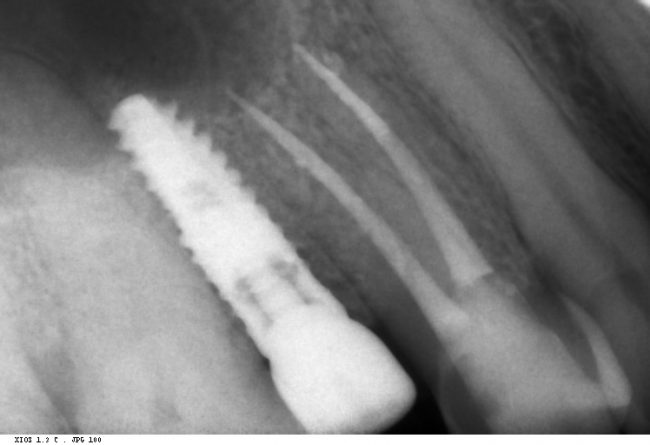

Кстати, обрати внимание на ширину альвеолярного гребня (левая картинка). Она чуть меньше 3 мм. Это объясняет, почему я засомневался в возможности установки имплантатов одновременно с остеопластикой. Понятно и без КЛКТ.

Возвращаемся к основной операционной области. Еще раз посмотрим на альвеолярный гребень, поофигеваем от его ширины и моих грандиозных планов:

Глянем на то, что получилось:

Для этого мы сделали КЛКТ:

И КЛКТ показала нам, что с имплантатами и окружающей костью всё зашибись. Через 12 лет после операции, отсутствия наблюдения, пофигизма в замене временных коронок! Нужны ли тебе еще какие-нибудь доводы в пользу долгосрочной эффективности метода?

Серия контрольных снимков на этапах: